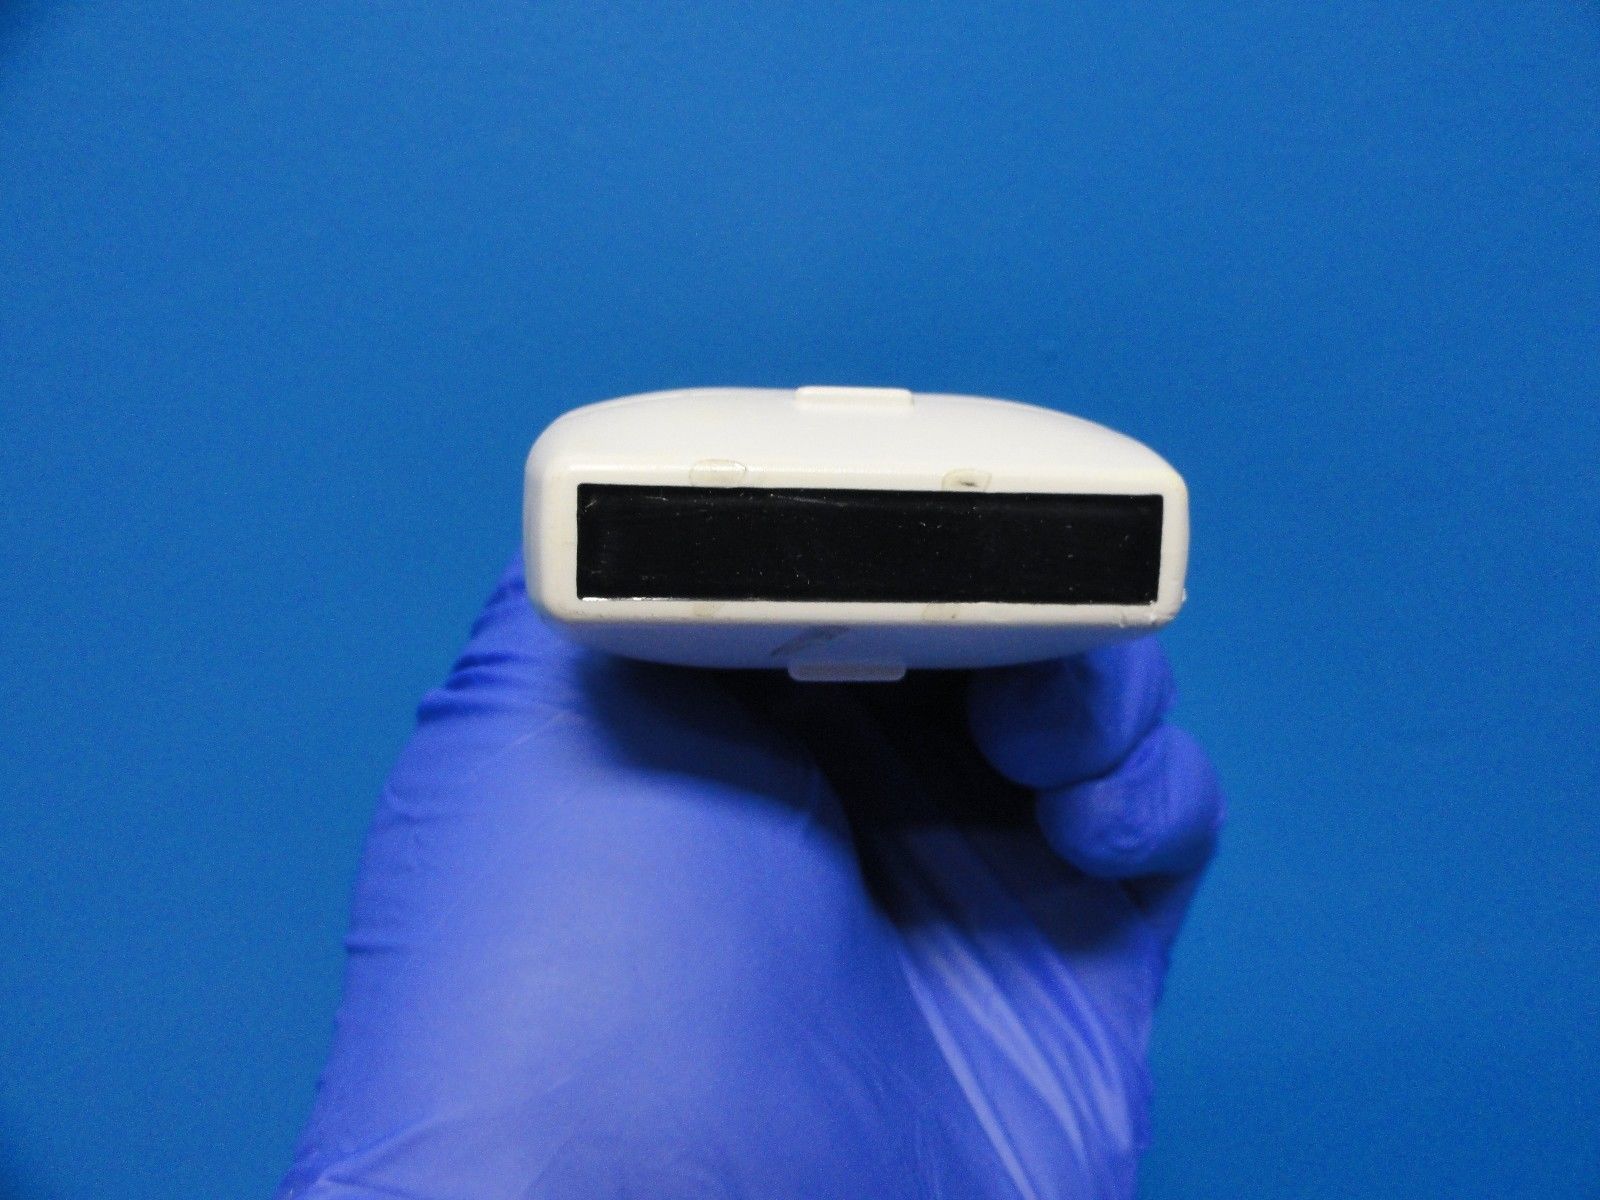

DIAGNOSTIC ULTRASOUND MACHINES FOR SALE

Samsung EC4-9/10ED Ultrasound Probe / Transducer

Sale price$ 10,545.18